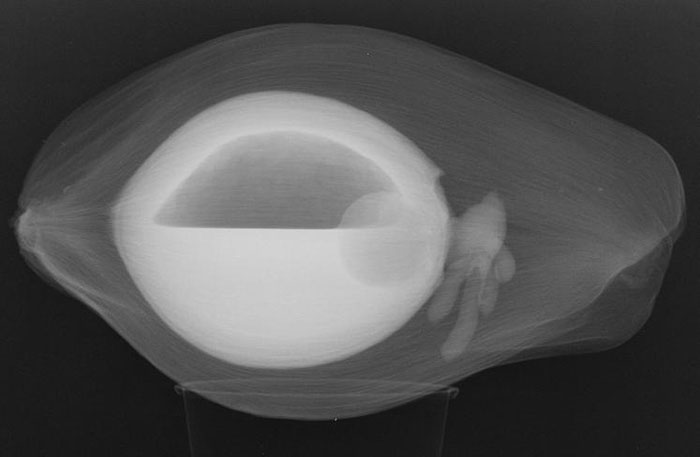

X-Ray Of A Pregnant Dog